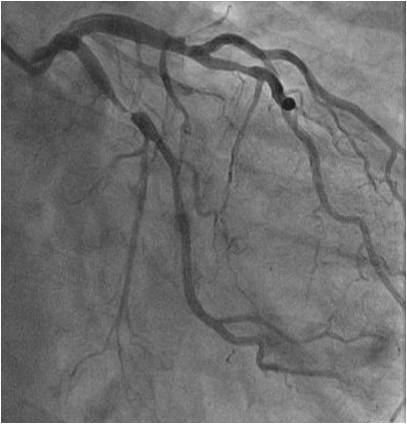

冠脉造影只能检测到5%的冠脉树,95%的冠脉微血管不可见